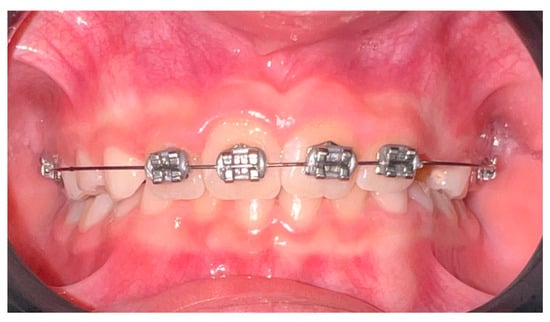

- Sockalingam, S.N.M.P.; Zakaria, A.S.I.; Khan, K.A.M.; Azmi, F.M.; Noor, N.M. Simple Orthodontic Correction of Rotated Malpositioned Teeth Using Sectional Wire and 2 × 4 Orthodontic Appliances in Mixed-Dentition: A Report of Two Cases. Case Rep. Dent. 2020, 2020, 6972196. [Google Scholar] [CrossRef]

| Wiedel, AP. et al, 2016 [84] | Randomized controlled | 62 children with anterior crossbite | Compare self-perceived pain and jaw function in relation to fixed vs. removable appliances | Questionnaires conducted over 8 weeks, VAS scales, functional questions, and randomized appliance allocation | Minor differences in discomfort were noted; both appliances were well tolerated and effective. |

| Da Silva, V. et al., 2023 [86] | Randomized clinical trial | 32 children (7–11 years old) | Compare efficacy and efficiency of clear aligners vs. 2 × 4 appliances in regard to mixed dentition | Digital dental models and 3D software were used. Patients were randomized into clear aligner or 2 × 4 fixed-appliance groups and treated for ~8 months. | Both methods showed similar efficacy; appliance choice can be based on clinician and family preference. |